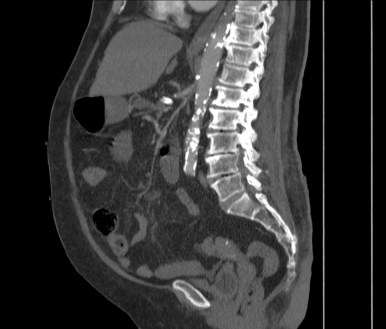

Paciente 89 años hospitalizada por dolor abdominal intenso y náuseas sin vómitos. El dolor es generalizado y no cede con tramadol.

Se realiza TC de abdomen en vacío y con contraste en fase portal:

Estamos ante un cuadro de isquemia intestinal en un paciente con bajo gasto cardiaco con afectación principal de asas intestino delgado, territorio vacularizado por la arteria mesentérica superior.